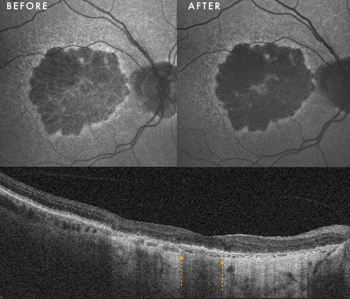

Fig 1. The large central drusenoid PED has resolved without any associated atrophy following PBM. There is also more definite ellipzoid zone line at the fovea after PBM. BCVA improved from 6/9 to 6/6

Case 1: Drusenoid PED resolution with RPE preservation

Drusenoid pigment epithelial detachments (PEDs) present a significant risk of progression to photoreceptor and RPE atrophy upon collapse.

Clinical presentation: A 60-year-old woman presented with large, central drusenoid PEDs in both eyes. Natural history data indicate that the resolution of such lesions is almost invariably accompanied by atrophy of the underlying RPE and overlying photoreceptors.

Response to therapy: Following PBM, one eye exhibited a remarkable anatomical response: the PED resolved and flattened, accompanied by a significant restoration of the ellipsoid zone on OCT. Crucially, this occurred without the expected RPE atrophy (See Fig 1 at the top of this article).

This structural success was matched functionally, with BCVA improving from 6/9 to 6/6. In the fellow eye, the PED remained structurally stable, yet she still achieved functional gain, improving from 6/30 to 6/24.

Clinical implication: This outcome suggests PBM may facilitate the metabolic clearance of sub-RPE deposits while sustaining cellular viability, potentially altering the typical course of PED collapse. Further cycles of PBM treatment and longitudinal follow-up will determine if her fellow eye eventually achieves a similar anatomical resolution.